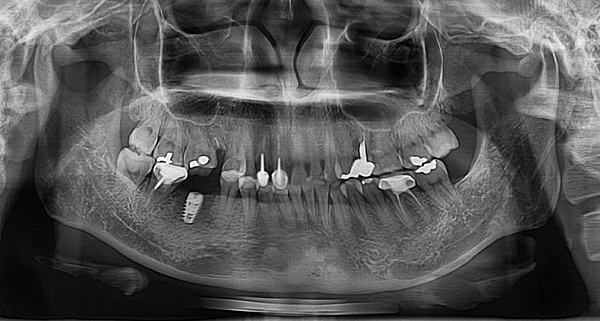

看X光照就知道我的缺牙很大洞,幾乎快可以塞下兩顆牙齒XD 評估的時候醫師也有跟我說,缺牙比較大的狀況下,選擇植牙效果會比較好,真的是跟醫師相見恨晚啊!

看x光就知道,植入植體的位置非常剛好,果然沒有選錯醫師!醫師說植體是未來裝上假牙的支柱,等傷口癒合、植體和骨頭連結度夠強後就可以開始戴上假牙。